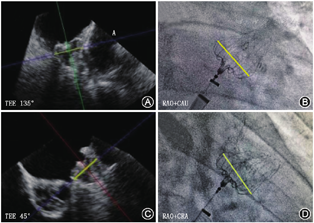

X线透视下评估PASS原则(视频9),总结如下:(1) P代表位置(Position):封堵器肩部位于心耳口部。X线透视下可行"三体位造影",分别查看封堵器上、下缘与左心耳开口的位置关系。建议露肩高度控制在封堵器直径的1/3以内。露肩通常在CAU 20°+RAO 0°~45°之间调整,将封堵器心房侧伞面的切线位显示清楚,结果与TEE对应角度吻合(图4)。(2) A代表锚定(Anchor):将止血阀略旋开,回撤外鞘距离封堵器伞面约2 cm,力量适度回拉释放手柄1.0~1.5 cm,并立即松开,该过程中有较明显的牵拉阻力,在X线透视下观察到封堵器与心耳壁同步运动,并且封堵器在牵拉后回弹明显,且无位置变化(可同时注射造影剂),器械稳定。当封堵器稳定性存疑时,可再次牵拉验证。取侧伞面切线位进行牵拉更易判断封堵器位置变化。(3) S代表尺寸(Size):在X线透视下进行压缩比的测量。可在右足或右肩位(调整至封堵器切线位)下曝光,量取封堵器最大直径计算压缩比,压缩比的计算方式为:(原始尺寸-展开直径)/原始尺寸×100%,数值推荐10%~30%为宜(图5)。可在LAO 40°~50°观察封堵器心房侧的整个伞面,过圆心连接帽进行最大直径测量,进行压缩比计算。(4) S代表密封(Seal):判断置入封堵器后是否存在PDL。X线透视下可行"三体位造影",分别查看封堵器边缘与心耳口部的位置关系,注意是否有造影剂从封堵器周围进入左心耳,若PDL≥3 mm,调整封堵器位置或更换封堵器。

需要转化术式的情况:(1)房间隔穿刺困难的患者,包括解剖因素、外科术后或曾多次穿刺及房间隔缺损封堵术后,若出现该情况,则建议全身麻醉;(2)造影显示不清、无法看清左心耳解剖,原因包括心耳结构复杂、鞘管轴向差及患者肥胖X线透视显影不清;(3)术中封堵效果不确定的患者,包括露肩、压缩比、稳定性、PDL大小以及对毗邻组织的影响,需要借助其他影像学手段进一步明确(图8)。如出现虽然牵拉十分稳定,但是无法准确测量封堵器压缩比或露肩,以及疑似PDL>3 mm等情况,为进一步确保封堵效果,建议采用TEE或ICE来验证(图10)。